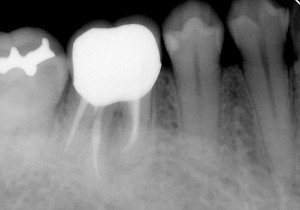

その後は、いろいろな器具を使いながらエンヤ~コ~ラ~と進めていくと・・・

こんな感じに無事終了することが出来ました。結構曲がりくねった神経の通り道ですね~。